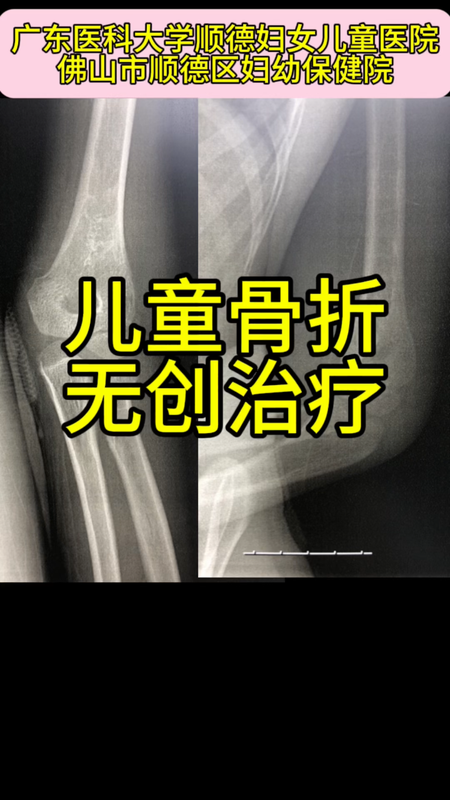

無創(chuàng)治療兒童肱骨髁上骨折: 8歲孩子不慎摔傷致肘部腫脹疼痛,外院拍片未見明顯骨折,休息一周后腫脹疼痛

無創(chuàng)治療兒童肱骨髁上骨折:8歲孩子不慎摔傷致肘部腫脹疼痛,外院拍片未見明顯骨折,休息一周后腫脹疼痛仍未消退。在我院重新拍肘關(guān)節(jié)標(biāo)準(zhǔn)正側(cè)位片,標(biāo)準(zhǔn)側(cè)位片發(fā)現(xiàn)肱骨髁上骨折且明顯移位,肱骨遠(yuǎn)端前傾角嚴(yán)重丟失,如不復(fù)位,骨折將畸形愈合,導(dǎo)致肘關(guān)節(jié)過伸畸形和屈曲活動受限。在我院予以無創(chuàng)手法復(fù)位,恢復(fù)肱骨遠(yuǎn)端正常前傾角,管型石膏固定4周。